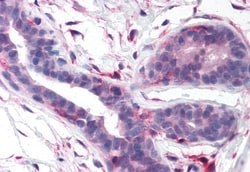

Percent identity with other species by BLAST analysis: Human, Gorilla, Gibbon, Monkey, Marmoset, Mouse, Rat, Dog, Bovine, Bat, Hamster, Elephant, Turkey, Chicken, Lizard (100%); Rabbit, Xenopus, Zebrafish (94%); Platypus, Pufferfish (88%). For IHC(P), use heat induced antigen retrieval in pH 6.0 citrate buffer. After incubation with the primary antibody, slides were incubated with biotinylated secondary antibody, followed by alkaline phosphatase-streptavidin and chromogen.

| Immunohistochemistry (Paraffin) | |